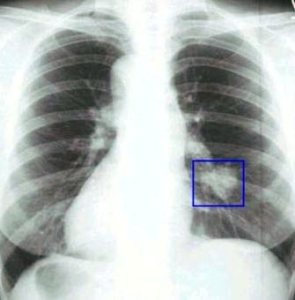

Рак легких – один из самых распространенных видов этого заболевания. В чем тут причина: загрязнение воздуха, распространенность курения или что-то иное, – доподлинно неизвестно. Одно можно сказать точно: болезнь эта лечится с трудом, но шансы все-таки есть.

Ранняя диагностика – главный фактор успеха!

Если вы живете не в самом благополучном в экологическом отношении регионе, если не можете избавиться от курения или работаете на вредном производстве, – важно регулярно проходить тщательный осмотр и сдавать анализы, которые позволили бы выявить раковые клетки при их наличии.

Учтите: операция на легких при раке возможна лишь на ранней стадии его развития. На более поздних, когда метастазы уже распространились на соседние органы, это часто бессмысленно. Поэтому, если вас что-то беспокоит, лучше пройти диагностику. При лечении на ранней стадии любая злокачественная опухоль может быть ликвидирована без серьезных последствий.